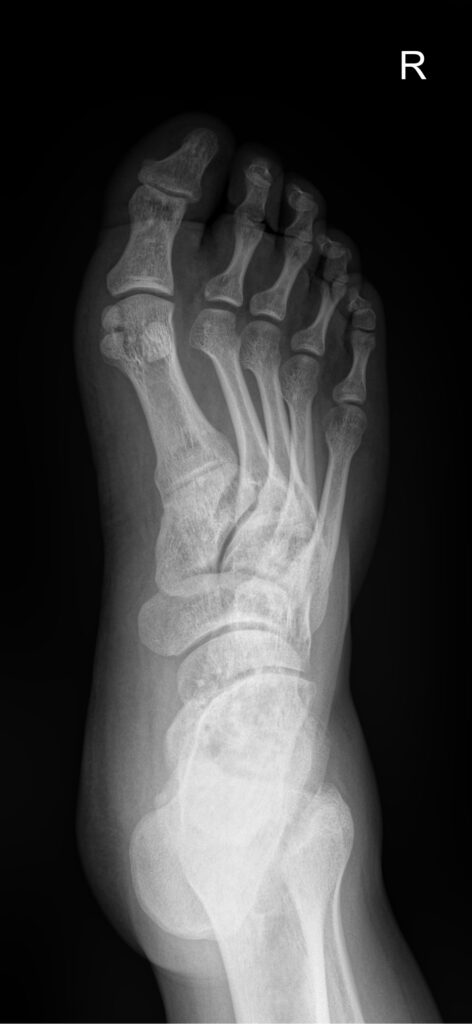

-голеностопный сустав (вывих, перелом, артрит, плоскостопие и др.);